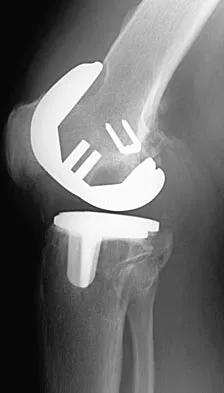

Figures 3a and 3b show the current radiographs of a 58-year-old man who underwent total knee arthroplasty with a cruciate ligament sparing prosthesis 7 years ago. Examination reveals boggy synovitis and moderate pain, particularly anteriorly. Management should consist of

Explanation

The patient has symptoms of synovitis that are most likely the result of the release of particles from the tibial polyethylene. While observation may be warranted in a completely asymtomatic knee, some intervention is indicated for this patient as there is clear radiographic evidence of lysis in both the tibia and femur. The decision about the extent of the revision should be made at the time of surgery. A limited incision technique is not indicated. Grafting (or using graft substitute) the defect is the most appropriate approach for treating the osteolytic lesions. While a posterior stabilized prosthesis might be the solution, surgical findings might dictate otherwise.